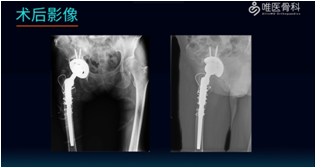

影像学检查:术前X线片提示右侧人工髋关节置换术后改变,髋臼假体松动。

安装髋臼假体:给予脉冲冲洗后,依次进行68mm Pinnacle-Gription髋臼假体的安装、钻孔、拧入螺钉和安装聚乙烯衬垫。

①充分冲洗后给予股骨髓腔扩髓、预绑钢丝,然后安装股骨假体(MP)远端,安装MP假体近端试模。

②根据臼杯前倾,调整股骨前倾,使联合前倾角在安全范围内。安装标准股骨头试模,并尝试复位,但是复位困难。遂给予依次组装不同尺寸的假体试模并进行复位,以确定合适的下肢长度、稳定性和偏距。

③假体大小确定后,仔细确认合适的股骨前倾角(参考髋臼杯的前倾角,使联合前倾角在安全范围内),然后安装标准股骨头试模并进行复位,检查髋关节稳定性和下肢长度。

④给予多重钢丝、钛缆捆扎修复截骨块。取下试模,安装陶瓷股骨头,复位后再次检查髋关节稳定性和下肢长度。